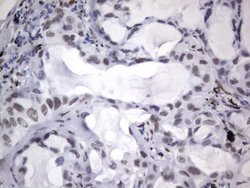

RBFOX1 Mouse anti-Human, Clone: OTI4F9, lyophilized, TrueMAB™

| Immunohistochemistry (Paraffin), Western Blot | |